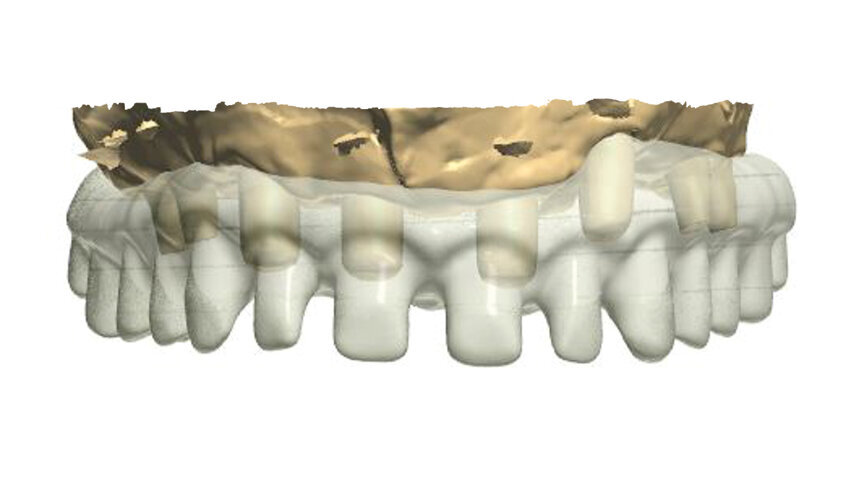

In order to prepare the bridge, a model was scanned and transferred onto a computer using software to design the bar (Fig. 1). The bar was designed by using special software in such a way that the whole design was transparent in the first phase so that the location of abutments and the position of the telescopic abutments at the frontal section could be visible (Fig. 2).

Having planned the proper shape and location of pillars for the porcelain crowns, the transparency was switched off (Fig. 3).

The next phase involved the planning of the size and shape of the final teeth, which, as porcelain crowns, will be glued onto the construction (Fig. 4). For that purpose, it is very helpful if on the design of the bar, a scan of the patient's temporary model prosthesis can be planted.

The patient must first approve the wax-up, in aesthetical and functional terms (Fig. 4). A computer programme for designing such constructions provides us with the possibility of viewing and designing the bar from all angles. Figures 5 to 9 show some exemplary prints of the views visible from the occlusal surface. Having finished the designing process, the bar should be visually inspected from the intragingival side (Fig. 10).